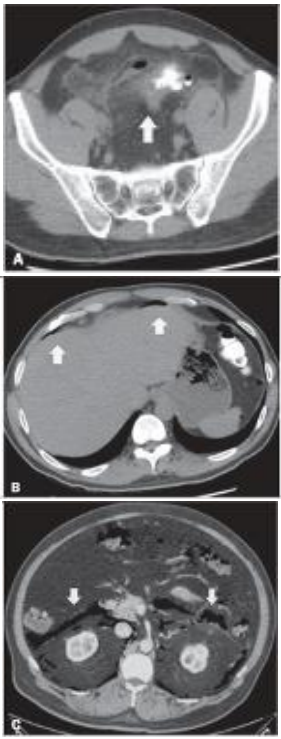

A avaliação da diverticulite aguda dos cólons tem na TC um ótimo método de diagnóstico.

Acerca da interpretação da TC acima, é correto afirmar que